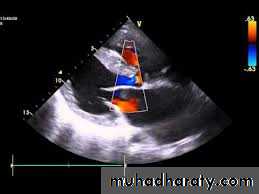

Echocardiography show the PDA and the cardiac chambers.